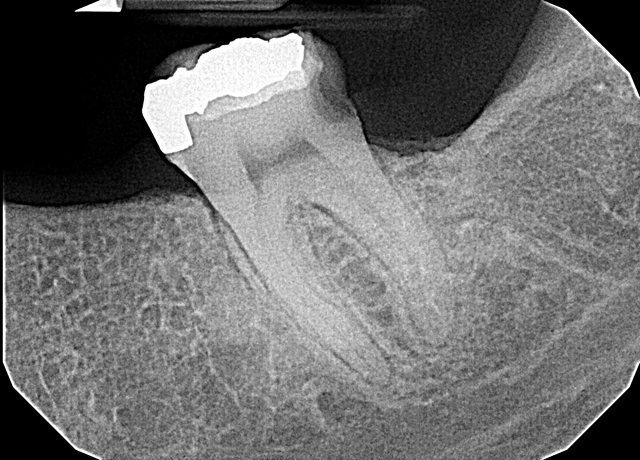

The patient is 26-year-old female with several missing teeth and gross decay of several others. She has neglected her dental care due to limited access and financial duress. The lower right second molar had previously been restored with amalgam. The amalgam had partially fractured out and there was a deep carious lesion with close proximity to the pulp (Fig. 1). The tooth was asymptomatic. The pulp tested vital with traditional pulp testing. Because of the deep decay and proximity to the pulp, I previously would have considered endodontically treating this tooth and then restoring with a passive post and core followed with a full coverage crown.

Fig. 1 Fig. 2